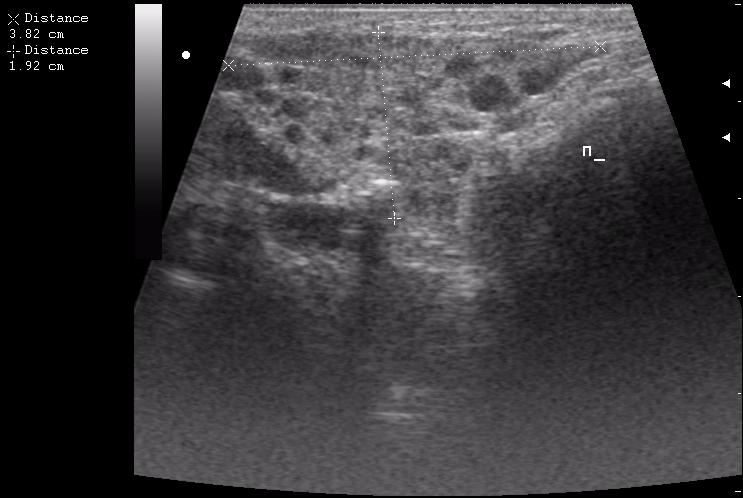

правая околоушная железа

расширенный выводной проток